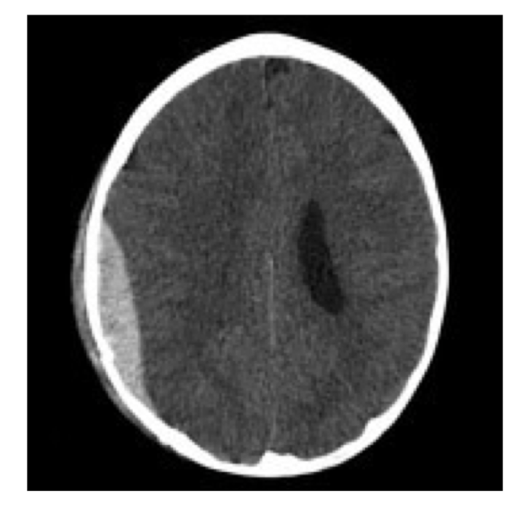

What is the protocol + pathology?

• CT non con brain

• Intraparenchymal

haemorrhage: brain bleed within the brain parenchyma

• Hyperattenuating mass posteriorly in the occipital lobe

• Midline shift

• Adjacent oedema.